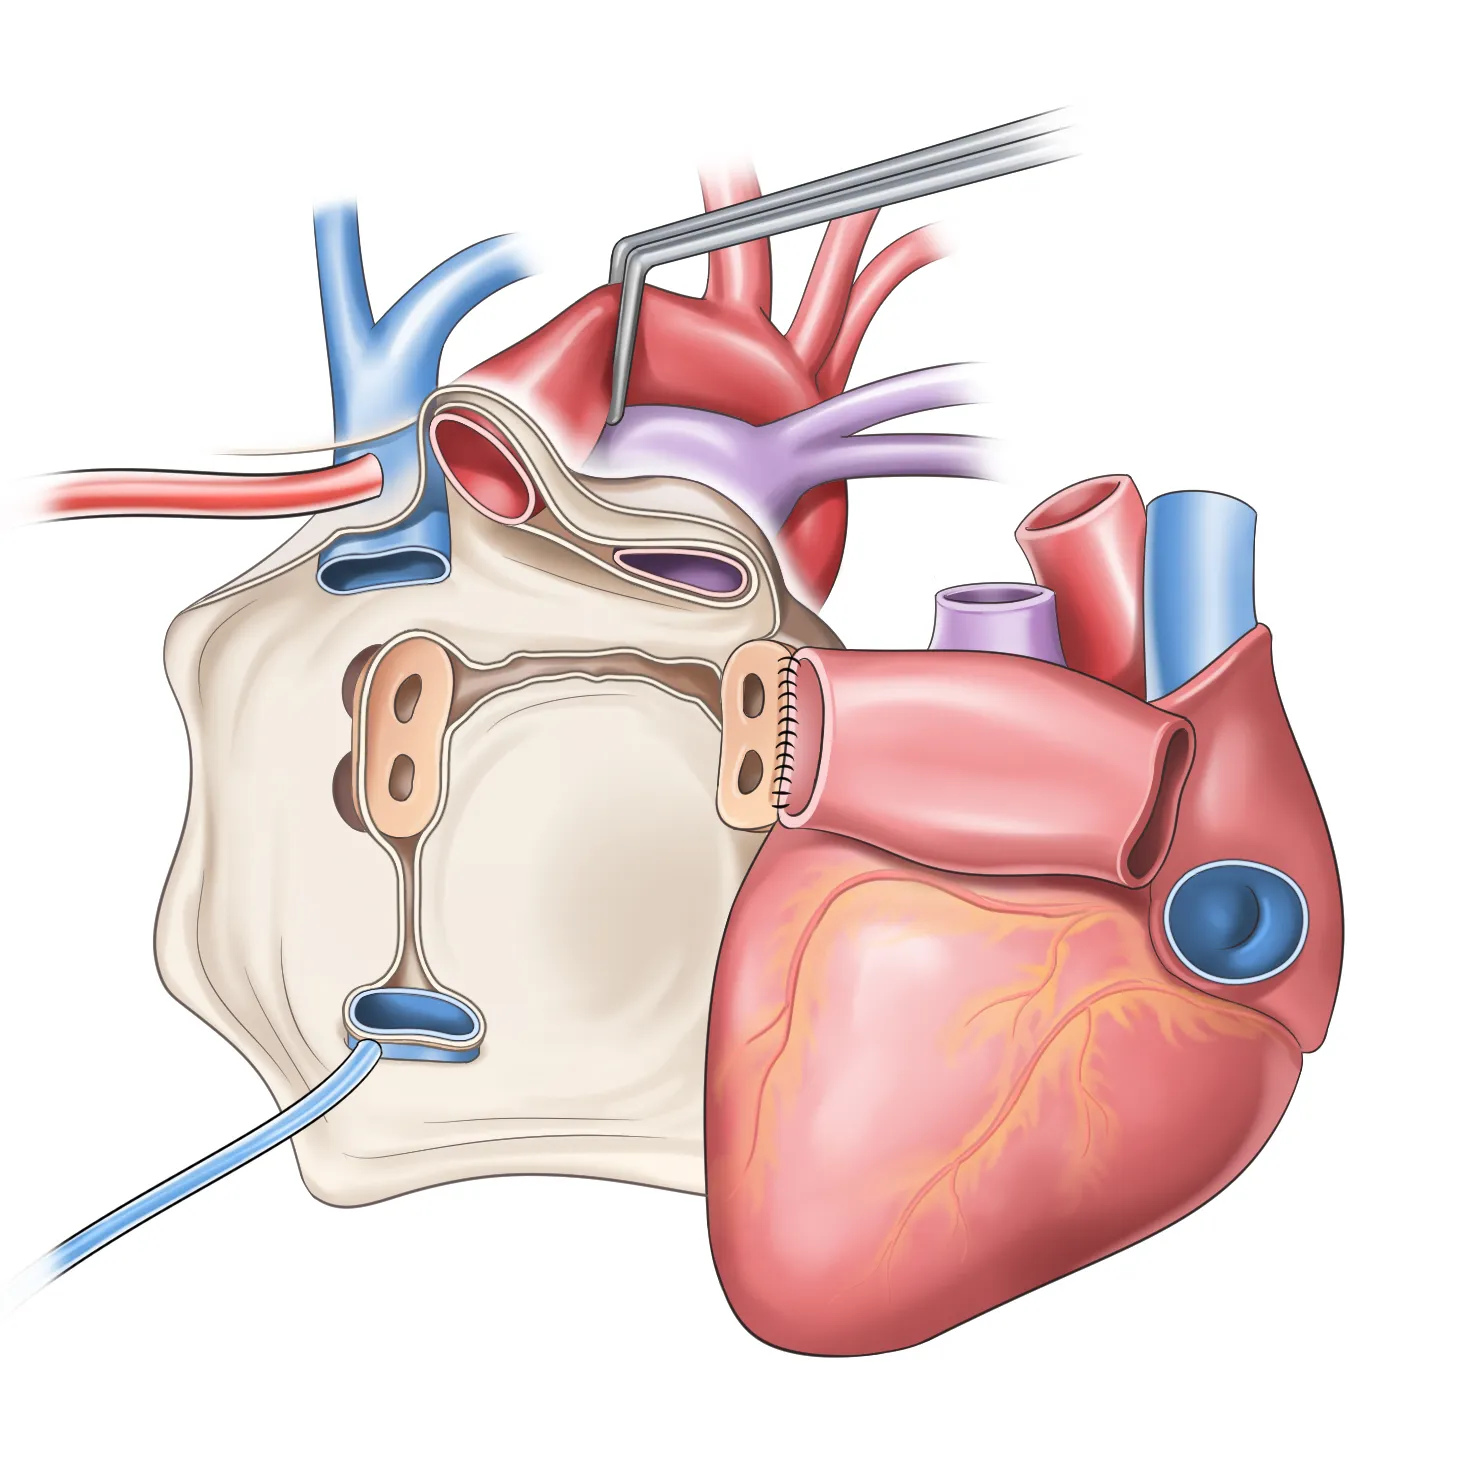

1. 심장 관련 원인

- 부정맥: 정상 심박수 범위 60-100회/분 이탈

- 심장 판막 이상: 증상 발현 시 심박수 변동 20% 이상

- 빈맥증: 휴식 시에도 심박수 100회/분 이상

- 서맥증: 심박수 60회/분 이하로 저하